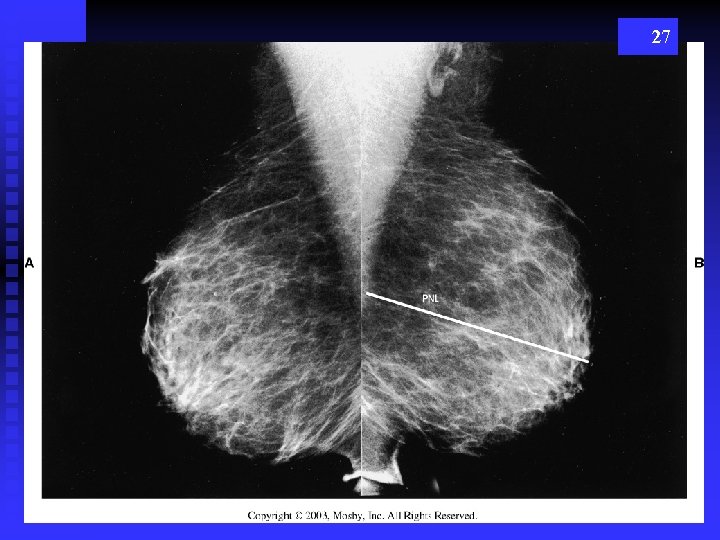

27